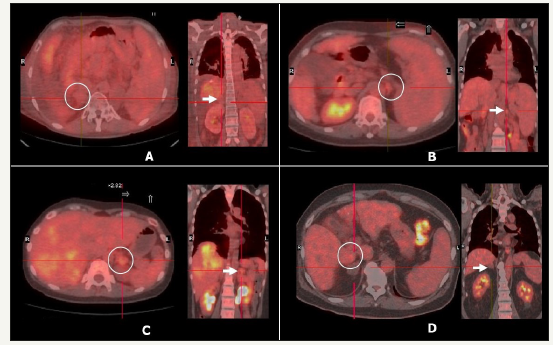

Four patients (mean age, 53 years; M: F, 2:2) underwent LDLT for HCC with single adrenal metastasis (right adrenal gland=2 patients; and left adrenal gland=2 patients). Figure 1 shows the PET scan images showing the adrenal gland metastasis.

This 50-year male patient of liver cirrhosis with a history of encephalopathy and variceal bleeding was diagnosed to have multiple HCCs over S5-7 and suspected right portal vein thrombosis. PET scan revealed right adrenal gland metastasis with no other extrahepatic metastatic disease (Figure 1A). Liver resection for HCC was not feasible due to Child C functional status of patient. LDLT with right adrenalectomy was performed. At 33rd post-LDLT month patient developed multiple lung metastases and received chemotherapy. Patient expired at 52nd month post LDLT due to intra-abdominal infection and overwhelming sepsis.

This 59-year-old female was diagnosed to have hepatitis C virus related HCC. During routine workup of the patient she was found to have metachronous left adrenal gland solitary metastatic lesion (Figure 1B). Due to underlying cirrhosis, hepatectomy was not possible. Hence, left adrenalectomy was performed, and patient received TACE for HCC. Sequential LDLT was performed after 7 months of adrenal gland resection as her liver functions deteriorated after second TACE that she received. After a follow up of 59 months, patient still remains recurrence free with normal graft functions.

43-year-female with a chronic hepatitis B viral infection status was diagnosed to have multiple HCC with left adrenal gland metastasis (Figure 1C). She received ABOi LDLT and left adrenalectomy as a single stage surgery. On second postoperative day, patient developed hepatic artery thrombosis that was treated by re-exploration and re-do hepatic arterial anastomosis. Her further course was without any complications and was discharged in third week post LDLT with stable liver functions. Patient developed lung metastasis and died due to respiratory failure after 28 months post-LDLT.

This 61-year-old male with chronic HBV carrier status was diagnosed to have HCC with solitary extrahepatic metastasis at right adrenal gland (Figure 1D). He received LDLT with left adrenalectomy as a single stage surgery. However, patient developed intrahepatic recurrence at 9 months post-LDLT and died due to liver graft failure (Table 1). In fourth patient, the histopathology showed mixed variant HCC with cholangiocarcinoma examination of the explant liver. The AFP levels were less than 100ng/ml. Follow up period ranged from 9 months to 59 months. Maximum survival achieved was 59 months in second patient who continues to have recurrence free survival.

Figure 1:PET-CT images of the patients showing solitary adrenal gland metastasis. A,B, C and D images show the adrenal gland metastasis in patient 1, patient 2, patient 3 and patient 4 in this series, respectively.